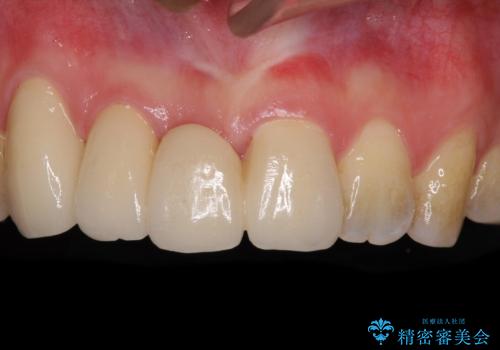

[ 矯正と補綴、総合歯科治療 ] クロスバイトを避ける前歯部審美ブリッジ

![[ 矯正と補綴、総合歯科治療 ] クロスバイトを避ける前歯部審美ブリッジの症例 治療後](https://seimitsushinbi.jp/wp/wp-content/uploads/2021/07/fcd77503a97e2f3a648f6e8698e34626-500x350.jpg?v=1626697051)